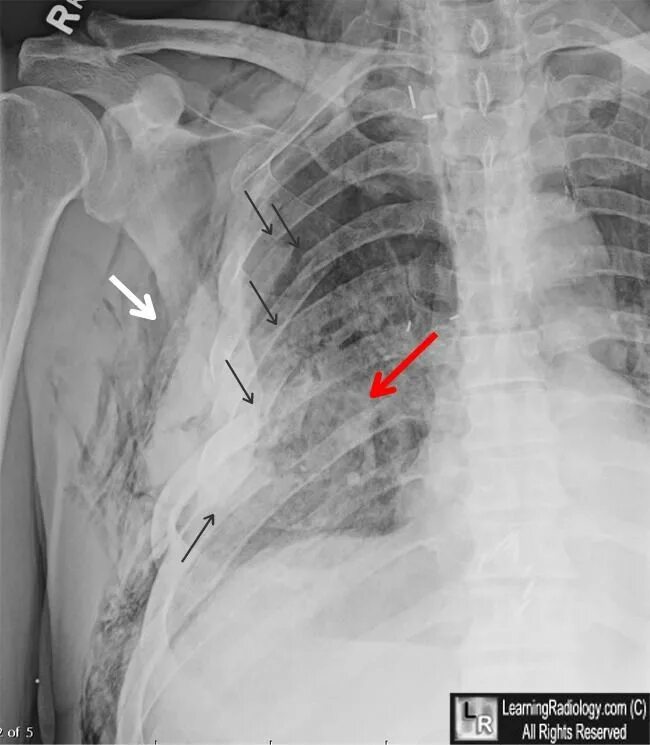

Множественные ребра